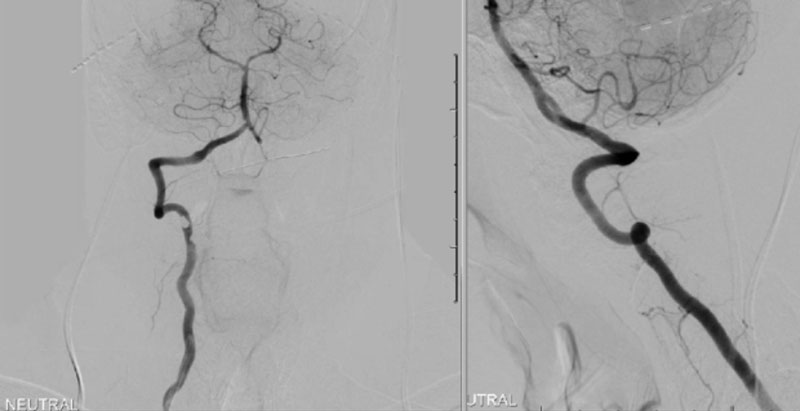

During neutral positioning, the vertebrobasilar circulation fills briskly from the Right Vertebral Artery. (Figure 4)

On rotation to the left, the patient experienced mild symptoms, however no significant Vertebral Artery or basilar reduction in flow was observed. On rotation to the right, the patient experiences slightly more moderate symptoms, however no significant Vertebral Artery or vascular reduction flow was observed. On hyper extension of approximately 10-15 degrees, passively performed by the patient until symptoms are reproduced, angiogram demonstrates complete occlusion of the right Vertebral Artery at approximately the C2-C1 level. (Figure 5)